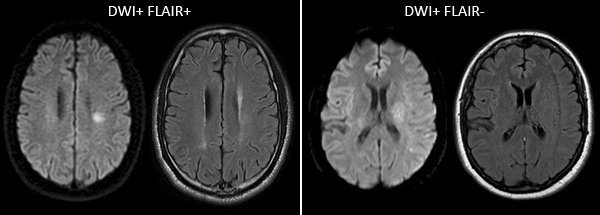

Если кровоизлияние определяют спустя 3 суток и более, более точным будет уже МРТ. Он лучше определит гематому, в которой кровь уже имеет окисленный, частично распадающийся гемоглобин.

• Неконтрастная компьютерная томография.

• Магнитно-резонансная томография.

Если кровоизлияние определяют спустя 3 суток или более, показательнее будет уже МРТ. Он лучше определит гематому, в которой кровь имеет окисленный, частично распадающийся гемоглобин.